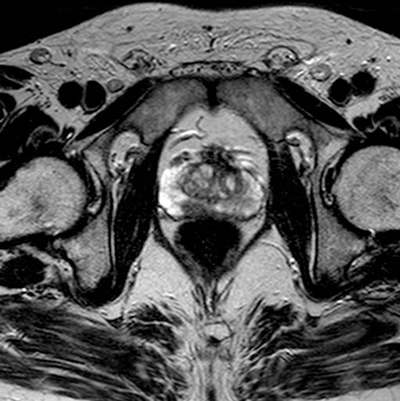

On T2-weighted images, the normal peripheral zone demonstrates homogeneous high signal intensity. The outer margin of the peripheral zone is demarcated by a thin rim of low signal intensity, which represents the true prostate capsule. The neurovascular bundles are low-signal intensity structures seen posterolateral to the true capsule and are surrounded by high-signal fat [4] (Figure 2).

Figure 2: Axial T2 image showing high signal peripheral zone

and low signal capsule and heterogenous central zone.